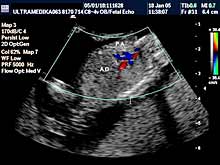

- 3D Sono CT SRCA PLODA (fetalna ehokardiografija) Prostorno, vremenska

korelacija ultrazvučnih markera prikazana multiplanarno predstavlja

dopunsku metodu u otkrivanju urođenih srčanih anomalija.

Napomena:

a)

Urođene srčane mane su 6 puta češće od hromozomskih anomalija i

njihova težina često zahteva prekid trudnoće. b)

Ovaj pregled je posebno registrovan za trudnoće koje su prethodno

imale plod sa srčanom manom ili kada u okviru standardnog pregleda

nisu dobijene sve validne ultrazvučne informacije radi pouzdanog

isključenja njihovog postojanja.

Mada je prva procena anatomije srca obavezna u I trimestru trudnoće,

konačna procena se mora završiti od 16 do kraja 24 nedelje gestacije

(6 meseci). Nakon toga procena osnovne anatomije je otežana i

rezervisana je za procenu hemodinamike srca!